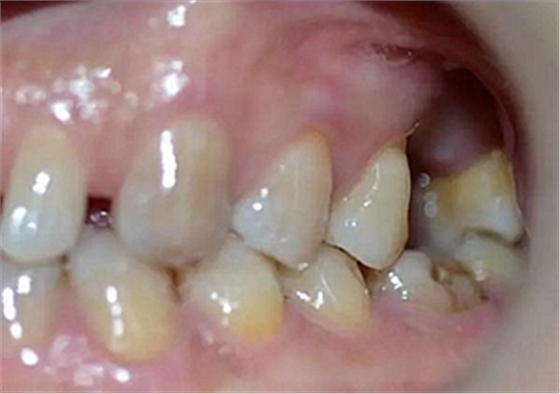

患者:男,37歲。左上后牙確實(shí)多年。既往體健,否認(rèn)麻醉和牙槽外科禁忌。

術(shù)前口內(nèi)照